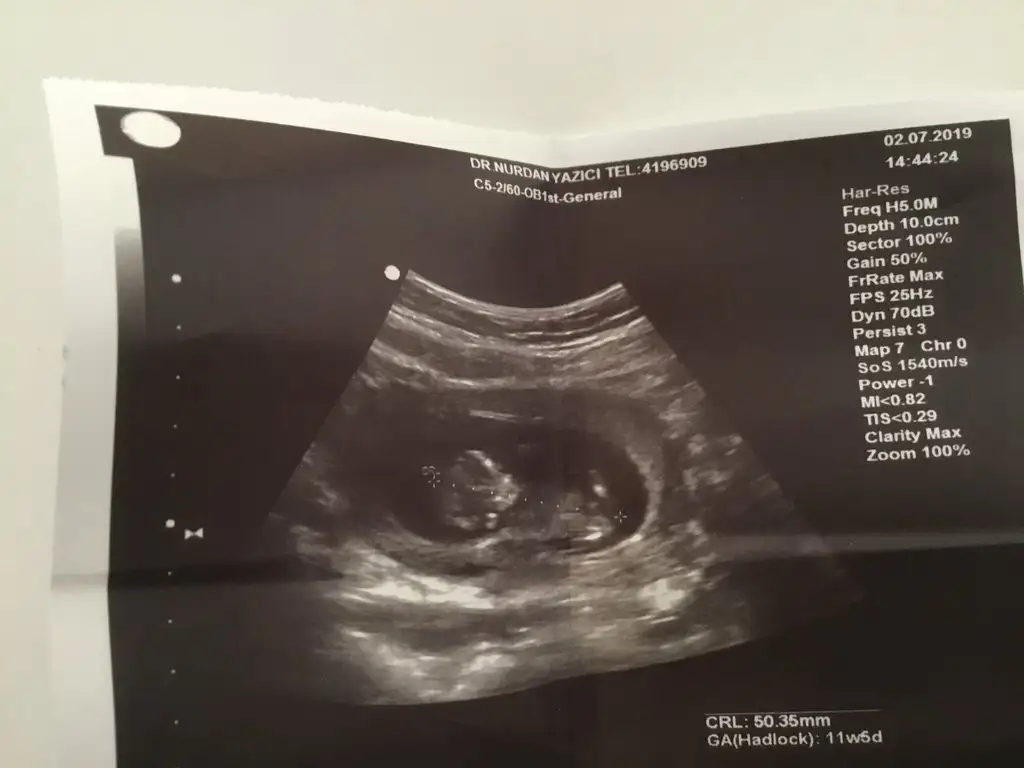

Göbek bağı da var ama, çok kıbırdamış hareketliymiş o an belliSelam kızlar bende ocak 2020 annesiyim. Cinsiyeti yarın öğrencem. Yanlız bi ultrason görüntüm var geçen haftaki ultrasondan, orda bi çıkıntı var ama dr cinsiyeti söylemedi. Sizce bu çıkıntı göbek bağı mı pipi mi?

Selam kızlar bende ocak 2020 annesiyim. Cinsiyeti yarın öğrencem. Yanlız bi ultrason görüntüm var geçen haftaki ultrasondan, orda bi çıkıntı var ama dr cinsiyeti söylemedi. Sizce bu çıkıntı göbek bağı mı pipi mi?

Ya tabi bu kendi yorumum o cikinti bana genital cikinti gibi geldi. Bacaklari baya kaldırmış. Bele paralel degil acili yukari doğru. Erkek sanki ama tabi yine cok guvenme banaAhh canım üşenmeden çizmişsin çok teşekkür ederim ilgilendiğin için. Nubu biliyorum duydum ama hiç anlamıyorum. Okadar arkada mı oluyor nub.

Teşekkür ederim yorumun için canım, benim de gönlümden erkek geçiyor bakalım hayırlısı yarın yazarımGöbek bağı da var ama, çok kıbırdamış hareketliymiş o an belliama bende erkeğe benzettim o ufak çıkıntı göbek bağı değil bence